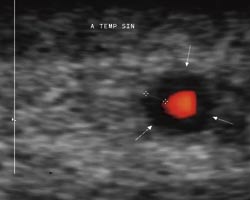

Pasient 2. En 66 år gammel kvinne hadde hypertensjon, men var ellers tidligere frisk. Etter en periode med luftveissymptomer fikk hun vedvarende tretthet, redusert allmenntilstand, vekttap og feber gjennom flere uker. Hun hadde også hatt smerter i tinningene og ansiktet (men dette ble ikke notert ved innleggelsen). Hun ble innlagt i medisinsk avdeling med mistanke om infeksjon. Ved innleggelsen var temperaturen 38,5 grader. Det ble notert god puls i tinningarteriene. SR var 107 mm, CRP 181 mg/l. Utredning kunne ikke avdekke infeksjonsfokus, og pasienten ble henvist til ultralyddoppler av tinningarteriene (med samme ultralydutstyr og teknikk som for pasient 1). Det ble bilateralt påvist en halo rundt arteriens lumen (fig 2a). Det ble så utført en kirurgisk biopsi av tinningarterien, og histologi viste granulomatøs betennelse med kjempeceller (fig 2b). Pasienten ble utskrevet med prednisolon 30 mg daglig med gradvis nedtrapping.

11 relevante studier ble selektert (11) – (21). Beskrevne diagnostiske kriterier i disse studiene var en lavekkogen (mørk) perifer brem rundt arteriens lumen (halo) med tykkelse 0,3 – 1,2 mm (11) samt stenose eller okklusjon av arterien.

Hos klinisk friske kontrollpersoner har man ikke kunnet påvise noen halo (11). Sammenliknet med histologi har man tolket haloen som uttrykk for infiltrasjon og ødem i karveggen (22). Sensitivitet i ti av disse studiene ble rapportert til 73 – 100 %, mens én studie med bruk av kun halo som kriterium hadde en begrenset sensitivitet på 40 % (16). I det største publiserte materialet med 751 pasienter hadde metoden en sensitivitet på 95 % i forhold til kirurgisk biopsi. Hvis man imidlertid sammenliknet med den endelige, kliniske diagnosen, var sensitiviteten for ultralyddoppler 88 %, mens den var 83 % for kirurgisk biopsi (17). I andre studier er det funnet en høy negativ prediktiv verdi, henholdsvis 96 % og 100 % (14, 15). En lav positiv prediktiv verdi på 50 % ble funnet i én studie, mens det i andre ble funnet verdier på over 95 % (20, 21).